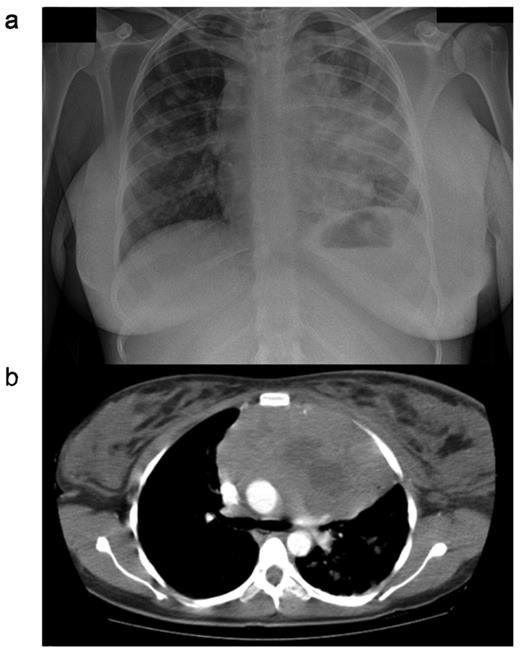

CXR (a) and CT (b) scan from a female patient presenting with primary mediastinal large B-cell lymphoma (PMBL). Note is the large anterior mediastinal mass, with areas suggestive of central necrosis. Marked breast edema is present.

PMBL normally presents with a bulky tumor in the anterior mediastinum that is rapidly progressive and may give rise to local compressive effects including dyspnea, cough, dysphagia and superior vena caval obstruction4 (Figure 1 ). The disease affects females more frequently than men, and peaks in incidence in the third or fourth decades. This is in contrast to the more elderly population affected by DLBCL.5 Tumor extension is local, invading lungs, chest wall, pleura and pericardium, often resulting in effusions (Table 1 ). Breast edema is common and hoarseness may reflect recurrent laryngeal nerve damage. Because the local effects are seen early, most cases present when the disease is limited to within the thorax. Extranodal sites, however, may be involved, particularly at the time of disease recurrence, with a propensity for involvement of the kidneys, adrenals, liver, ovaries and central nervous system. Bone marrow infiltration at presentation is rare.